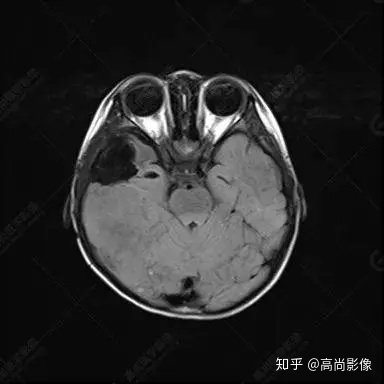

右側(cè)顳葉腫瘤切除術(shù)后(具體不詳):右側(cè)顳部骨質(zhì)不連續(xù)呈術(shù)后改變,右側(cè)顳葉術(shù)區(qū)見片狀長(zhǎng)T1長(zhǎng)T2信號(hào)影,F(xiàn)LAIR呈低信號(hào);術(shù)區(qū)后方右側(cè)顳枕葉見一巨大占位性病變影,邊界欠清,大小約6.2×5.8×4.3cm(前后×左右×上下),信號(hào)不均勻,T1WI呈等稍低信號(hào)間雜少許高信號(hào),T2WI呈高稍低混雜信號(hào),DWI示部分病灶彌散受限,相應(yīng)ADC圖減低,磁敏感序列見部分呈極低信號(hào),增強(qiáng)掃描可見明顯不均勻強(qiáng)化,鄰近硬腦膜及小腦幕增厚并明顯強(qiáng)化;另延髓右前方及右側(cè)橋小腦角區(qū)見一不規(guī)則形異常信號(hào)影,大小約3.2×1.3×3.7cm(左右×前后×上下),呈長(zhǎng)T1稍長(zhǎng)T2信號(hào),F(xiàn)LAIR呈等信號(hào),DWI未見受限,增強(qiáng)后明顯均勻強(qiáng)化,鄰近腦膜明顯強(qiáng)化。鄰近腦實(shí)質(zhì)及右側(cè)顳角明顯受壓;左側(cè)大腦半球未見局灶性信號(hào)異常,中線結(jié)構(gòu)稍左移。

右側(cè)顳葉腫瘤切除術(shù)后:現(xiàn)術(shù)區(qū)后方右側(cè)顳枕葉及延髓右前方占位,右側(cè)顳枕部硬腦膜及小腦幕明顯強(qiáng)化,結(jié)合既往影像資料,考慮為胚胎源性惡性腫瘤,如非典型畸胎樣/橫紋肌樣瘤(AT/RT)或原始神經(jīng)外胚層腫瘤(PNET)。